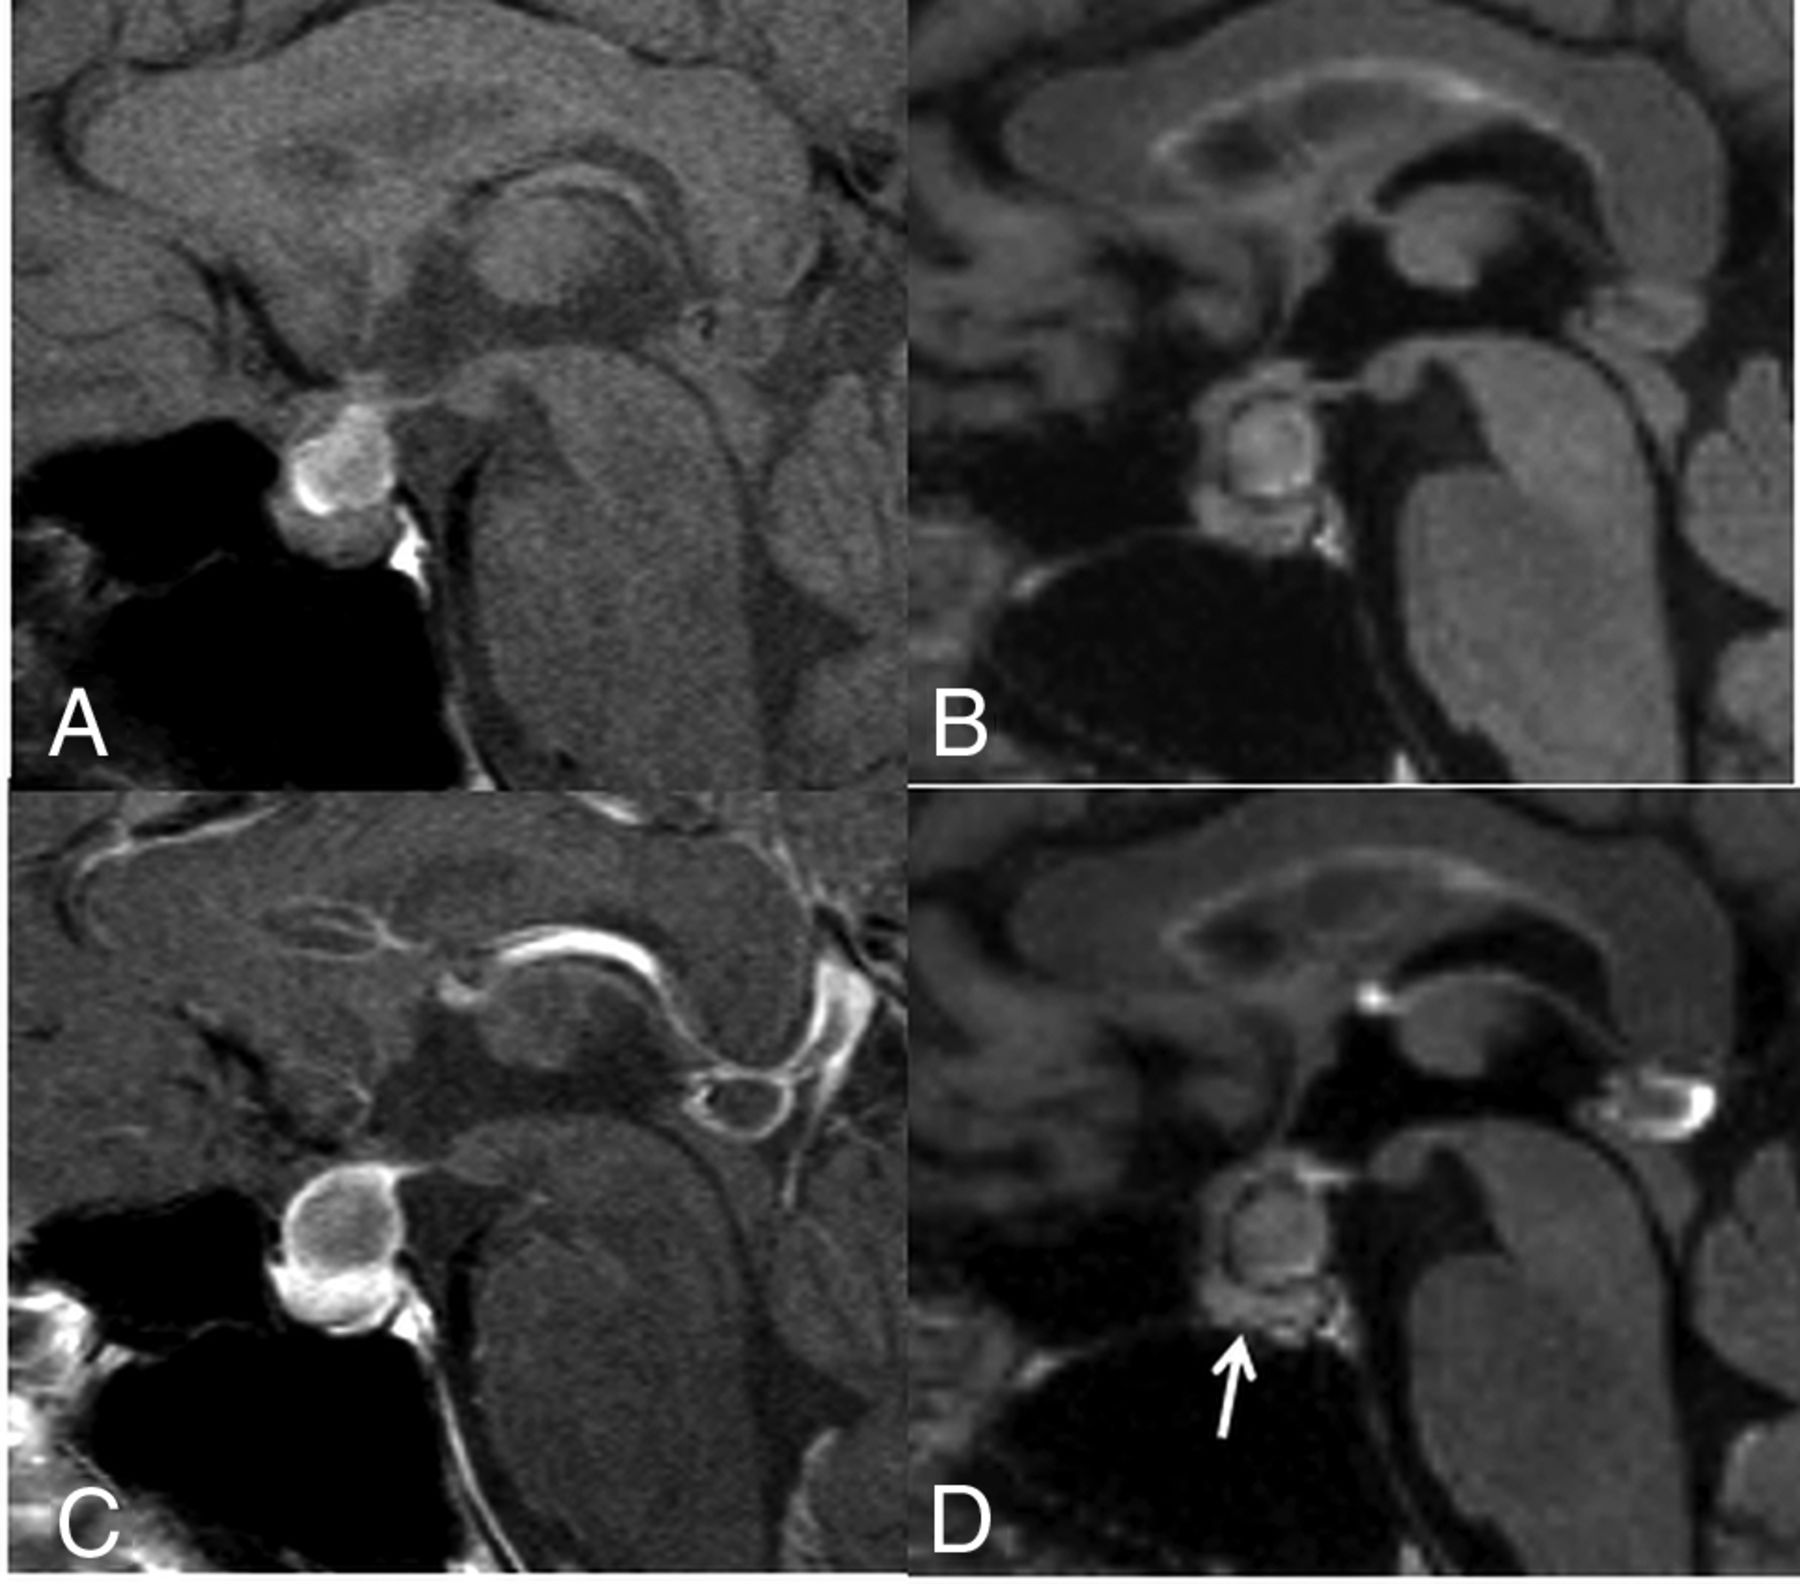

A 23-year-old woman with RCC. Compared with the precontrast T1WI (A), the postcontrast T1WI (C) demonstrates enhancement in most of the cyst wall (grade 2). Compared with the precontrast 3D T2-FLAIR image (B), the postcontrast 3D T2-FLAIR image (D) shows grade 1 enhancement of some of the cyst wall (arrow). In the blinded reading study, the confidence scale of this lesion was probably an RCC (scale 2) at both the first and second interpretation sessions.